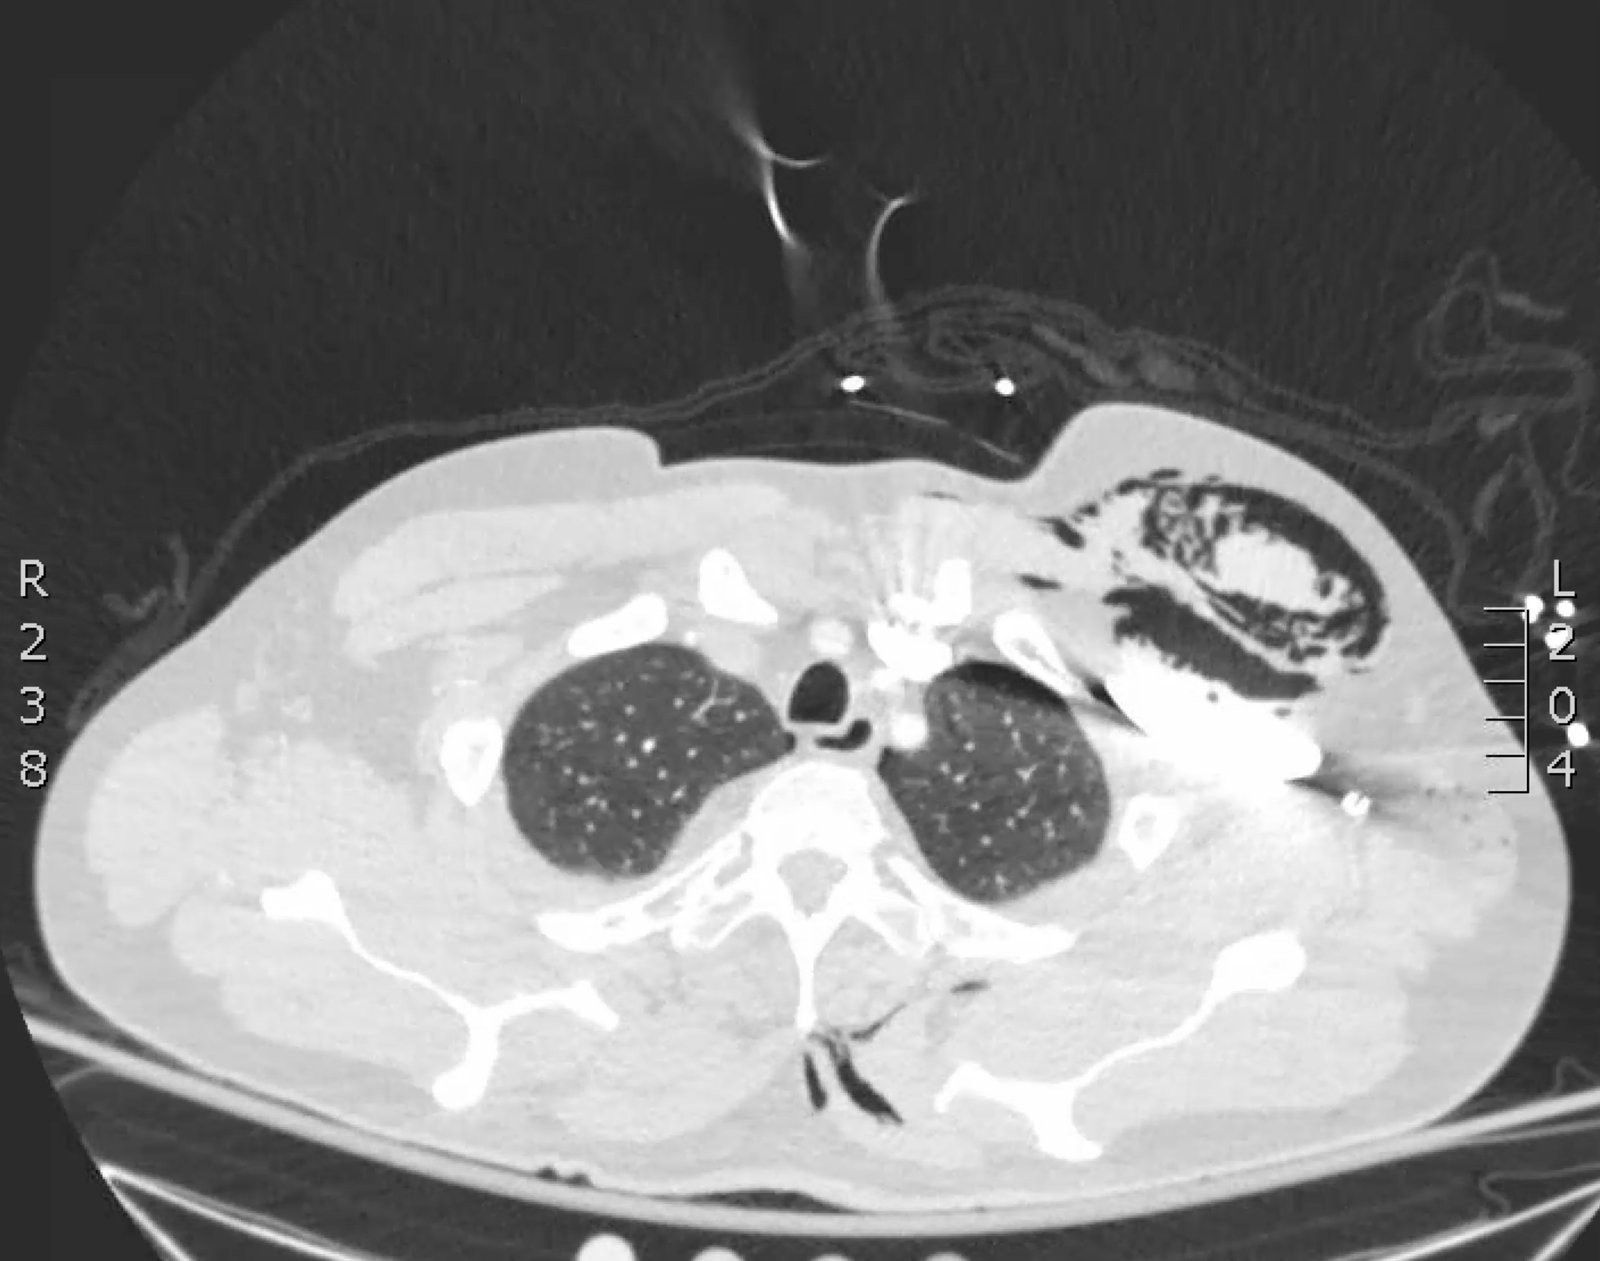

Plain film anteroposterior (AP) radiography of the chest shows left-sided subcutaneous emphysema (red arrow) with overlapping muscle striations of the pectoralis major (green arrow). After chest tube placement (blue arrow), AP chest radiography shows persistent left-sided subcutaneous emphysema (red arrow). CT of the chest shows pneumomediastinum (blue arrow), left apical pneumothorax (pink arrow), and subcutaneous emphysema (red arrow) at the level of T2. At the level of T6, rib fractures can be visualized on the CT (yellow arrow). At the level of T8, left sided pneumothorax is also seen (pink arrow) as the absence of lung tissue on CT.